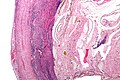

Acute appendicitis. H&E stain. | |

| LM | neutrophils in the muscularis propria |

- Neutrophils in the muscularis propria - key feature.

- +/- Vascular thrombosis (and necrosis) - known as gangrenous appendicitis.[6]